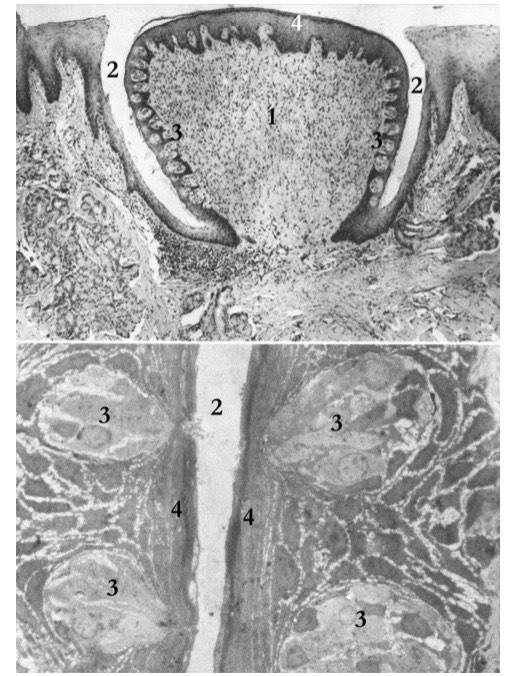

Гистологическое строение небной миндалины: 1 — крипта, 2 — лимфоидные фолликулы, 3 — капсула, 4 — устье крипты (лакуна)